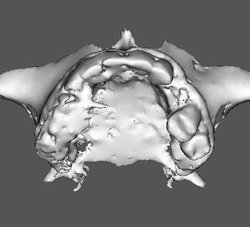

PROTOTIPAGEM

A prototipagem biomédica é o processo de construção de modelos físicos da anatomia humana por técnicas de prototipagem rápida. Esses modelos são baseados nas tomografias computadorizadas dos pacientes, desta forma, os protótipos são individualizados e representam com fidelidade a estrutura anatômica.

A Clinica Serraro gerencia todo o processo de envio das imagens do paciente até o centro de prototipagem, e você recebe o protótipo em seu consultório.

Tipos de protótipos: